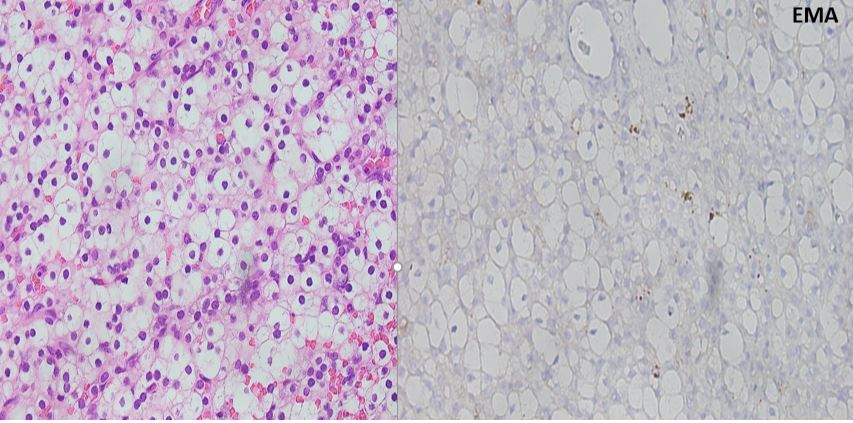

A 58-year-old woman presents with a 4.7 cm ovarian mass. The patient has a history of smoking, HTN, and DM2.  No definitive crystals are seen in the tissue sections examined. IHC images are shown.

Steroid cell tumor NOS is the correct diagnosis. The tumor cells are SF-1+, inhibin +, calretinin+, EMA-, PAX8-, and CAIX-.  All of the other and choices would be in the differential.  Leydig cell tumors have an identical immunoprofile, but Reinke crystals would be present and are required for the diagnosis.  Clear cell carcinoma of the ovary can form solid groups of clear cells, but the cells would be EMA+ and PAX8+ and negative for the typical sex cord tumor markers.  Metastatic clear cell renal cell carcinoma may show similar clear cell morphology, but would have a different immunoprofile including being  PAX8+, CAIX+, and EMA+. Metastatic adrenal cortical carcinoma would also be a consideration if there was history of an adrenal mass. The immunoprofile would be essentially the same.